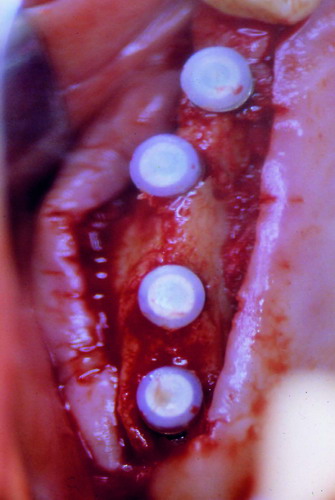

LA OCLUSIÓN MUTUAMENTE PROTEGIDA ES UN VIEJO CONCEPTO QUE CONSISTE EN LA MUTUA INTERACCIÓN DE LOS DISTINTOS GRUPOS DENTARIOS ENTRE SI. DE ESTA FORMA, LA TABLA PREMOLAR / MOLAR DE AMBOS HEMIMAXILARES ANTAGONISTAS, DETIENEN EL CIERRE MANDIBULAR EN CÉNTRICA, LOS CANINOS DISCLUYEN LAS PIEZAS POSTERIORES DURANTE LAS TRANSTRUSIONES, Y EL GRUPO INCISIVO LO MISMO DURANTE LAS PROPULSIVAS. SIN EMBARGO, DICHO CONCEPTO ES LIMITADO A LAS PIEZAS DENTARIAS, SIN TENER EN CONSIDERACIÓN LA IMPORTANTE FUNCIÓN QUE RECAE SOBRE LA ATM Y EN EL SOPORTE DE PRESIONES DURANTE ESTA DINÁMICA. ES ASI QUE EN EL AÑO 1981, EL DR. ANIBAL ALONSO GENERA EN LA CIUDAD DE BUENOS AIRES UN CONCEPTO MAS AMPLIO QUE DENOMINÓ : OCLUSION MUTUAMENTE COMPARTIDA. REF I EN EL QUE AMPLÍA EL CONCEPTO ANTERIOR, HACIENDO PARTÍCIPE A LA ATM EN LA MISMA. CUANDO EXISTE CARENCIA DE PIEZAS DENTARIAS POSTERIORES, YA SEA DE UN SOLO LADO O DE AMBOS , EL CIERRE MANDIBULAR ES DETENIDO POR LAS PIEZAS RESTANTE, FORZANDO A LA ATM A SOPORTAR PRESIONES MUY SUPERIORES A AQUELLAS PARA LAS QUE ESTA PREPARADA. FIG1 FIG2 FIG3 LUEGO DEL ESTUDIO CLÍNICO DE RIGOR, DONDE SE EVALÚA RADIOGRÁFICA Y PERIODONTALMENTE, SE PROCEDE A TOMAR MODELOS DE ESTUDIO Y MONTAR EN ARTICULADOR SEMIAJUSTABLE, SOBRE EL CUAL SE REALIZA UN ENCERADO PROGRESIVO DE DIAGNÓSTICO, A PARTIR DEL CUAL SE CONFECCIONA UN JUEGO COMPLETO DE PROVISIONALES DE AMBAS ARCADAS , INCLUYENDO LAS PIEZAS FALTANTES. SE ABORDA EL CASO YA QUIRÚRGICAMENTE DONDE EN UNA PRIMERA ETAPA SE TALLAN PRIMARIAMENTE LAS PIEZAS DENTARIAS Y SE PROCEDE, EXODONCIANDO EL INCISIVO CENTRAL SUPERIOR DERECHO, A REALIZAR UNA ROG(REGENERACIÓN ÓSEA GUIADA), PARA INMEDIATAMENTE INSTALAR PARTE DE NUESTROS PROVISORIOS EN LA GUIA ANTERIOR. SE ADAPTAN A LOS SECTORES POSTERIORES LAS PRÓTESIS REMOVIBLES QUE PORTABA, Y SE ESPERAN CUATRO MESES, AL CABO DE LOS CUALES SE REALIZA UN ESTUDIO CON DENTASCAN, MEDIANTE EL USO DE UNA FÉRULA RADIOLÓGICA CON TUBOS METÁLICOS , QUE NOS SERVIRÁ TAMBIÉN DE GUÍA QUIRÚRGICA. PROCEDEMOS ENTONCES A LA IMPLANTACIÓN DE LOS SECTORES EDÉNTULOS MEDIANTE IMPLANTES ROSCADOS Y TÉCNICA SEMI SUMERGIDA. TRANSCURRIDAS OCHO SEMANAS OBSERVAMOS UNA CORRECTA SALUD PERIMPLANTARIA, Y REALIZAMOS LA INSTALACIÓN DE LOS ABUTTMENTS ALCANZAMOS ENTONCES EL PUNTO EXACTO DONDE DEBEREMOS COMENZAR A RECONTRUIR EN FORMA PERMANENTE. PAZ DEL SISTEMA: CENTRICIDADARTICULAR-PAZ MUSCULAR-ESTABILIDAD- -ACOPLAMIENTO. BASES FUNDAMENTALES DE LA OCLUSIÓN ORGÁNICA FIG41 FIG42 PROCEDEMOS NUEVAMENTE A TOMAR IMPRESIONES, EN ESTE CASO DEFINITIVAS , MONTAR NUEVAMENTE EN ARTICULADOR, Y CONSTRUIR LAS RESTAURACIONES PERIFÉRICAS TOTALES EN BASE A PORCELANA SOBRE ORO GALVANIZADO. REF. II SOBRE LAS MISMAS TERMINADAS Y YA EN BOCA, CHEQUEÁMOS TODOS LOS ELEMENTOS QUE CONSTITUYEN UNA REHABILITACIÓN ORAL INTEGRAL, DESDE LA SALUD ENDODONTICA DE PIEZAS TRATADAS O NO, LA SALUD PERIODONTAL, EL AJUSTE PERIFÉRICO DE LAS RESTAURACIONES, LA ESTABILIDAD EN LA ATM, Y LAS FUNCIONES OCLUSALES, CHEQUEOS ESTOS QUE SE REPETIRAN EN CADA UNO DE LOS CONTROLES POST OPERATORIOS. FIG46 FIG47 FIG48 FIG66 FIG67 REFERENCIAS: REF I: OCLUSIÓN Y DIAGNÓSTICO EN REHABILITACIÓN ORAL REF. II ELECTROFORMACIÓN EN ODONTOLOGÍA RESTAURADORA.